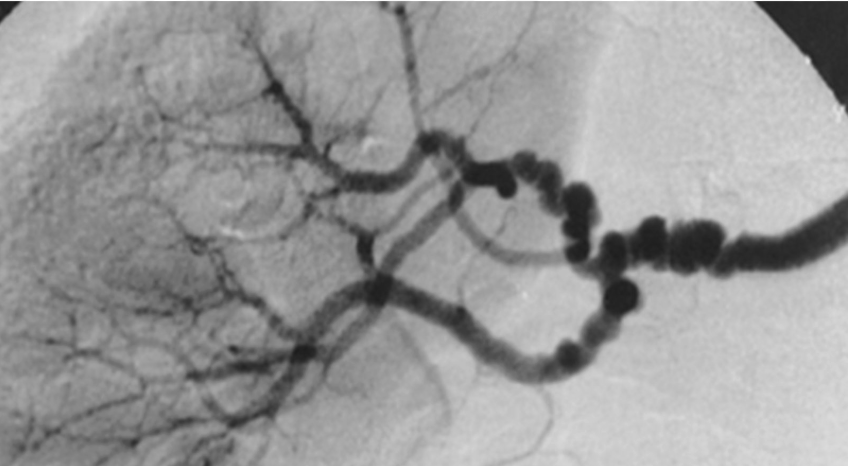

RAS Imaging: Catheter Angiography

Gold standard

Catheter + dye to visualize arteries